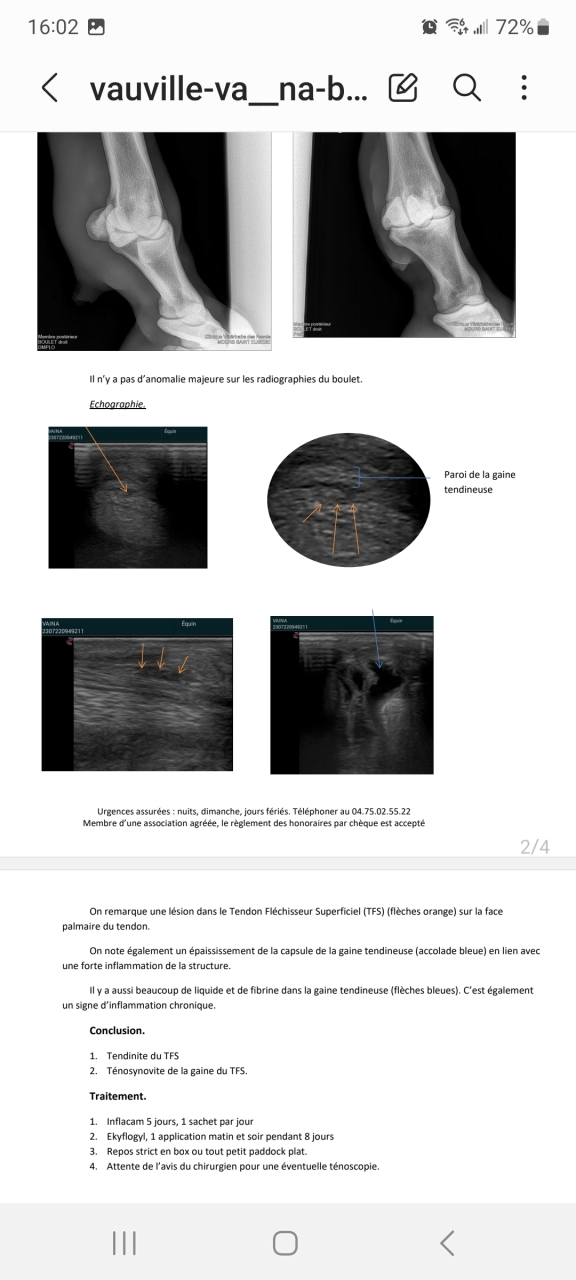

| Dire merci | Lésion du tendon superficiel, grosse inflammation de la gaine et gros épanchement. Donc on attend l'avis du chirurgien si il faut opérer. Inflammation de la parois de l'os mais légère là où elle s'est mise coup. La premier veto à pas fait les radios et l'écho au bon endroit. Donc on a pas pu comparer l'évolution. Voilà voilà on est parti pour quelques mois de soin. |

| Dire merci | Je vous met le compte rendu de l'echo ![]() |

Par kagnotte : le 23/07/23 à 16:06:33

| Dire merci | Et les radios![]() |

| Dire merci | Donc voilà je pense qu'on est parti sur quelques mois de galère. Et si certain ont des expériences sur ce type d'intervention je prends. Je ne sais pas encore quelle décision prendre. |